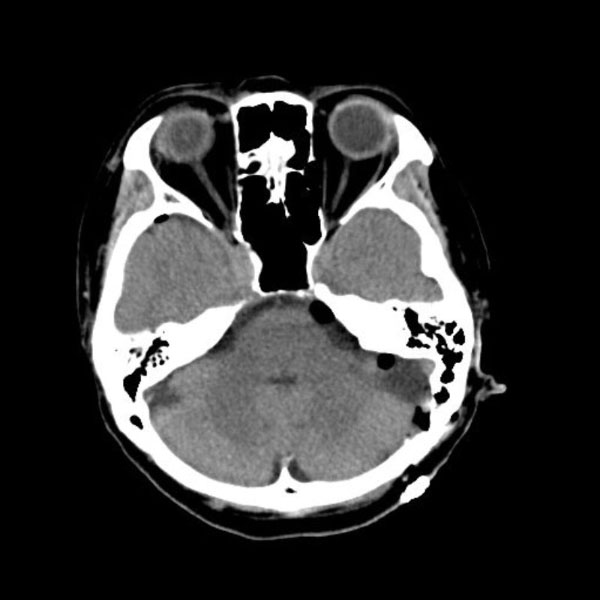

手術後

(CT)